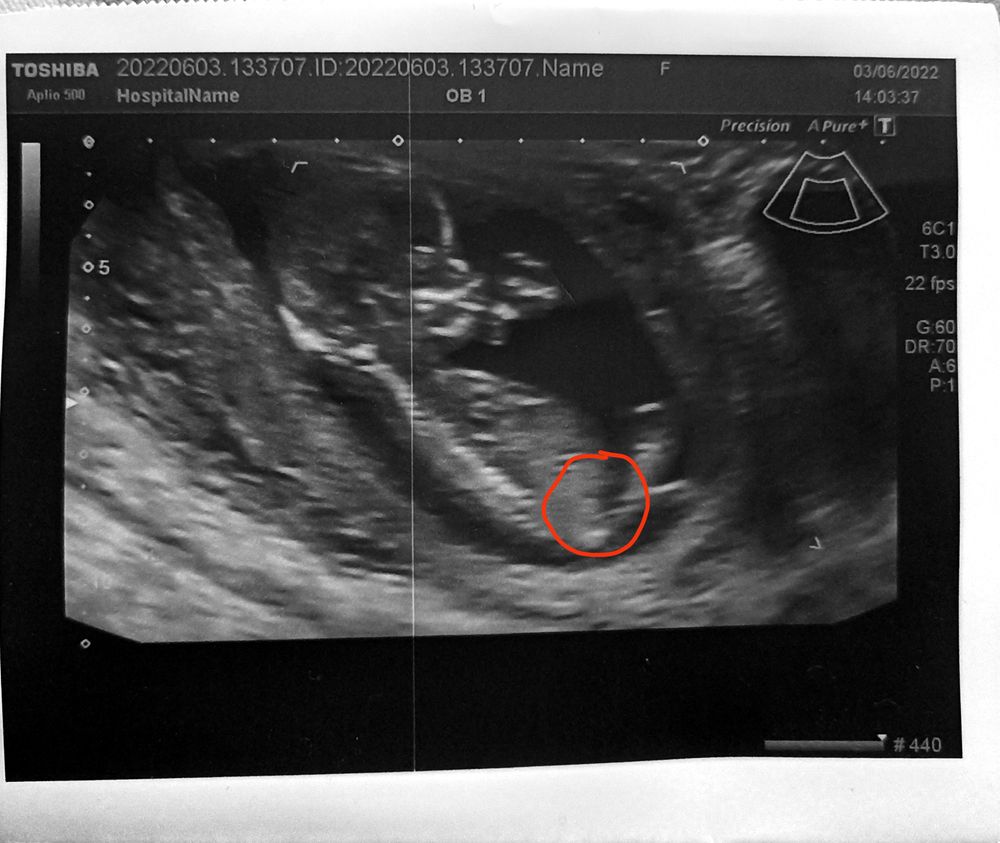

1 скрининг

Изображение

Девочки, подскажите кто разбирается, вот результат первого скрининга по Узи сказали все норм, по крови смотрю тоже заключение норм, интересны результаты насколько низкие риски?